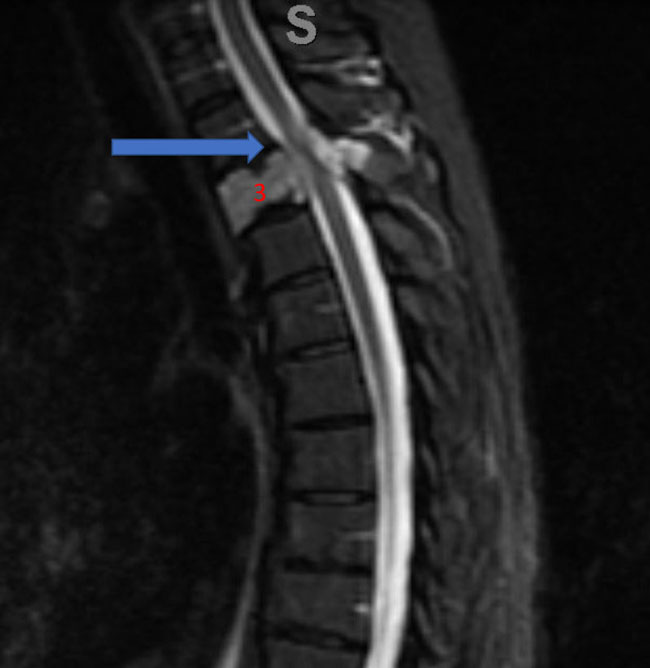

Spinal angiography showed a very hypervascular lesion fed predominantly by the right supreme intercostal artery (Figure 2. A, B).

Figure 2. (A, B) Selective angiography of the right supreme intercostal artery demonstrates extensive hypervascularity of this aggressive T3 hemangioma.

No spinal artery contributions were found to arise from this right T1-T3 pedicle. Superselective WADA testing was performed with Brevital injected through the microcatheter, which failed to elicit changes in the intraoperative monitoring, confirming safety to proceed with devascularization of this pedicle and tumor. This was performed with 100-300 micron particles achieving an excellent devascularization (Figure 3. A, B).